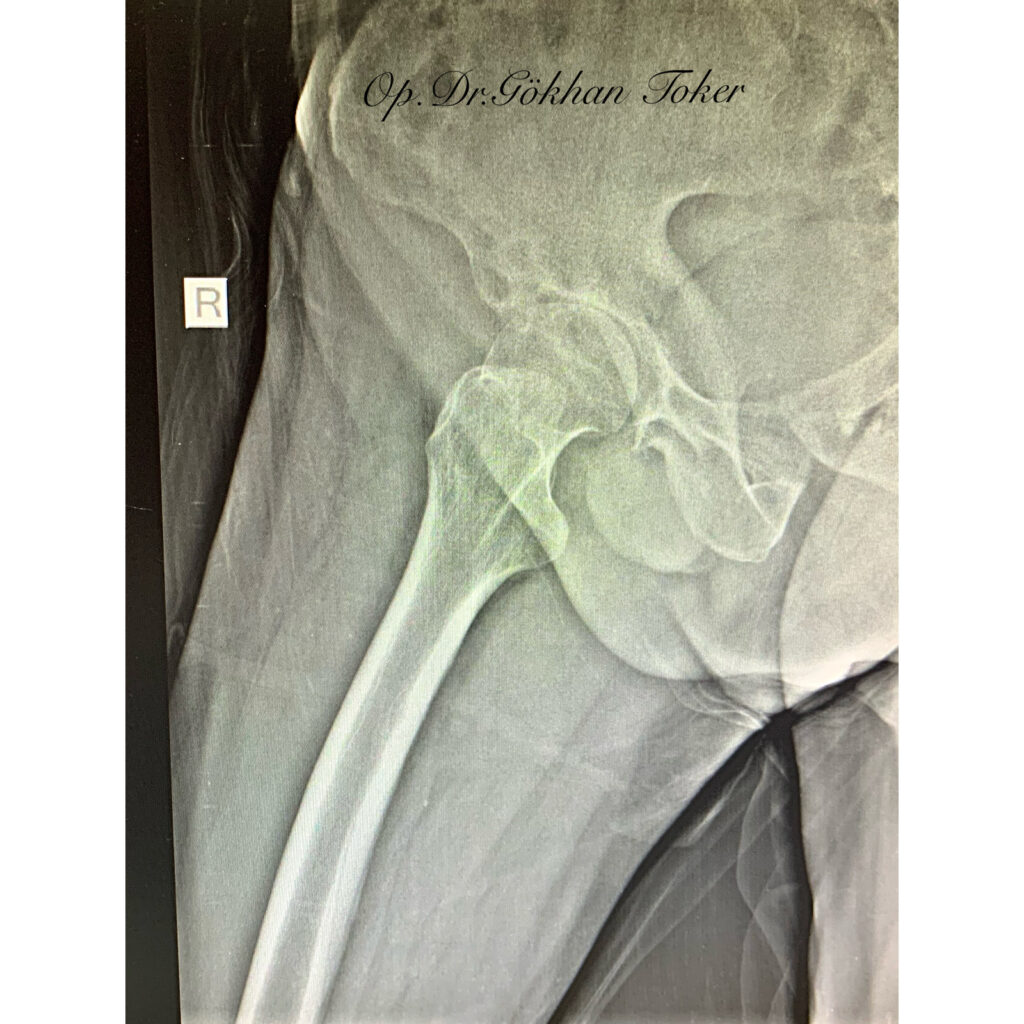

Ç.A.